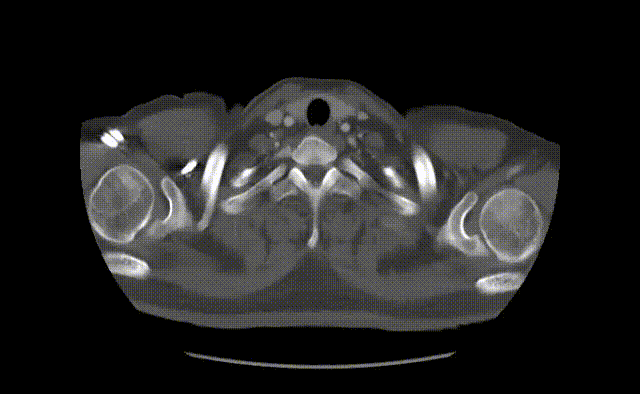

基本情况&CTA详解

患者男性,33岁,就诊6小时前出现剧烈胸部疼痛。患者既往无高血压、糖尿病等病史。于急诊科行全主动脉CTA检查。CTA提示患者B型夹层,破口紧邻左锁骨下动脉后缘,巨大升主动脉瘤,弓上三分支未受累及,左侧椎动脉优势。结合患者体征及家族史,推测为马凡综合征。

gore医疗怎么样「胸有乾坤」可调可控 分毫必争—GORE®TAG® 可主动调控胸主动脉覆膜支架治疗B型主动脉夹层伴升主动脉瘤病例报道_https://www.jmylbn.com_新闻资讯_第6张

gore医疗怎么样「胸有乾坤」可调可控 分毫必争—GORE®TAG® 可主动调控胸主动脉覆膜支架治疗B型主动脉夹层伴升主动脉瘤病例报道_https://www.jmylbn.com_新闻资讯_第7张

巨大升主动脉瘤